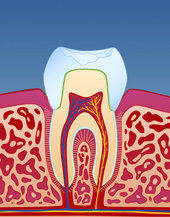

I tenner med store fyllinger, er tannsubstansen rundt fyllingen svekket. Når man tygger, kan det etter hvert utvikles tynne sprekker i tannen. Disse sprekkene utvikler seg under fyllingen og forløper vanligvis på skrå bort fra tann-nerven. Over tid kan slike sprekkdannelser medføre at en del av tannen knekker og faller ut. I noen tilfeller knekker tannen fordi man tygger på noe hardt, men ofte er dette ikke tilfelle. Det er heller den totale belastningen over tid som er utslagsgivende og tidspunktet for tannfrakturen er ofte tilfeldig.

Dersom en tann knekker på denne måten, bør man kontakte tannlege snarest for å få den reparert.